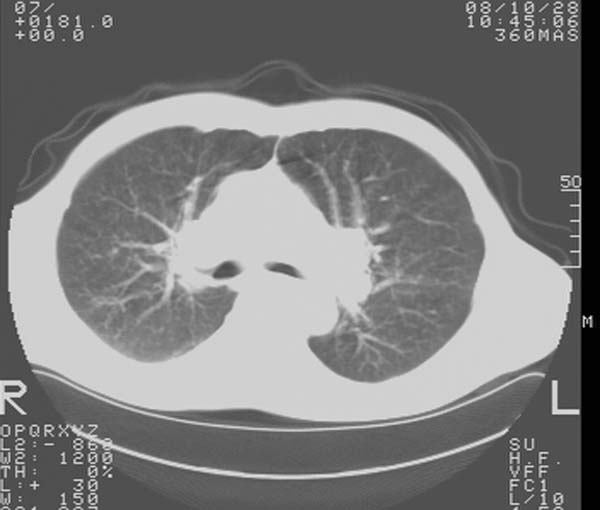

m,65y。半年前发现颈小结节,逐渐增多增大,现双侧耳后、颌下及颈部表浅淋巴肿大。胸片示双肺门增大。外院曾穿刺诊断为淋巴结核。在我科作胸腹部ct,我们觉得外院病检有误。现将图像上传请战友讨论。

纵隔内及腹膜后广泛淋巴结肿大,脾大,肝内似可见低密度影,结合病史半年前发现颈小结节,逐渐增多增大,现双侧耳后、颌下及颈部表浅淋巴肿大。考虑淋巴瘤。

纵隔,双肺门腹膜后多发淋巴结重大,非融合,肝脾轻度肿大,双肺野弥漫性小结节;考虑淋巴瘤,结节病可能性

纵隔内,双肺门、腋窝及腹膜后多发肿大淋巴结影,肺内小结节影,肝脾体积增大,支持淋巴瘤。肝内多发低密度影,考虑小囊肿。